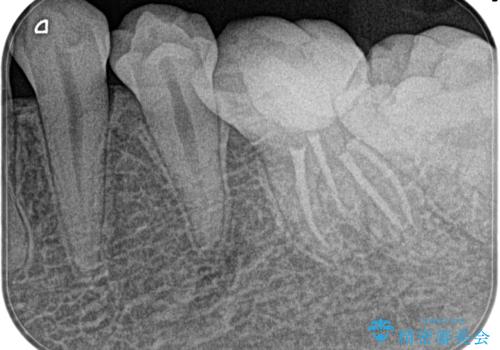

昨晩から激痛。精密根管治療

- 奥歯がズキズキ痛いことを主訴に来院されました。

検査の結果、診断を症候性不可逆性歯髄炎、症候性根尖性歯周炎とし抜髄を行っております。

- 精密根管治療(イニシャルケース,大臼歯):122,000円、ファイバーコア:22,000円費用は治療当時の料金となります

根管充填はCWCT。

根管形成はマルテンサイト相を有するNi-TIロータリーファイル(NEX MS) 使用。